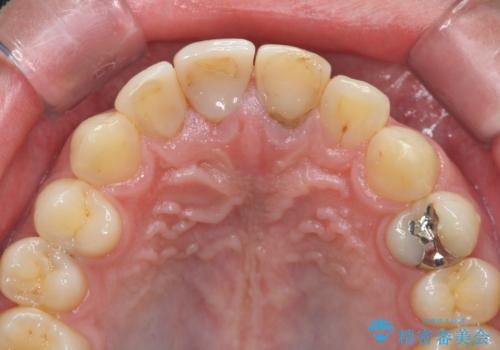

前歯の変色 審美性の改善

- 前歯の変色や形態を含む、見た目を改善したいと希望され来院されました。

視診・X線検査・歯周組織検査より下記のような問題が列挙され、長期的な予後を見込むために一つづつ問題の解決を計ります。

・不十分な根管治療 →マイクロスコープを用いる精密根管医療

・歯の変色 →ジルコニアクラウンの製作

・歯肉縁下カリエス →部分矯正による歯の挺出・歯周外科